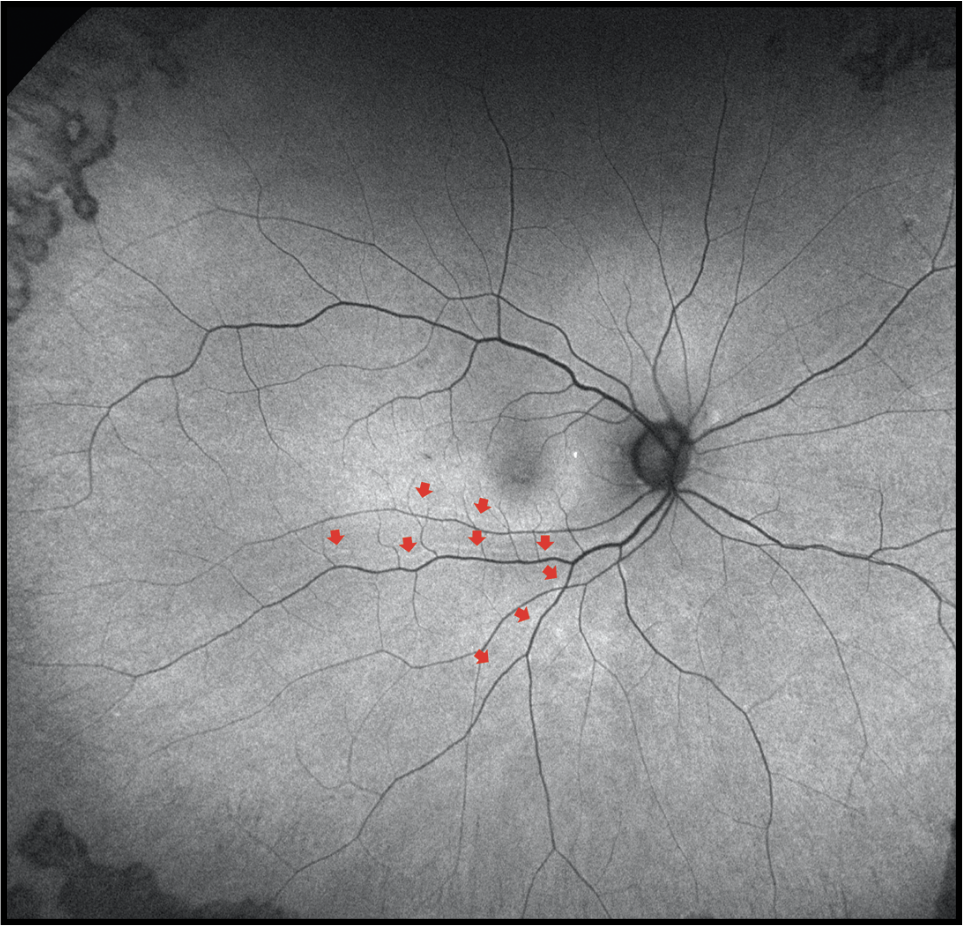

| Figure 3. Fundus autofluorescence three months after retinal detachment repair demonstrates anatomic reattachment with retinal displacement as evidenced by presence of retinal vessel printings (red arrows). |

Researchers have shown recent interest in retinal displacement detected by the presence of retinal vessel printings on FAF imaging (Figure 3) after RRD repair. This is another important imaging biomarker that has been associated with suboptimal functional outcomes after RRD repair when OCT doesn’t find discernible abnormalities. Swiss investigators demonstrated that the presence of retinal displacement is associated with worse metamorphopsia.19 Another large study by our group illustrated that the presence of retinal displacement was associated with worse aniseikonia.20

Researchers in the United Kingdom found that the amplitude of retinal displacement was associated with worse BCVA.21 Because of these inconsistent findings, our group recently conducted a large comprehensive retrospective study that considered all imaging modalities and functional outcomes. Our findings indicated that the presence of retinal displacement had a significant impact on both BCVA and aniseikonia.22